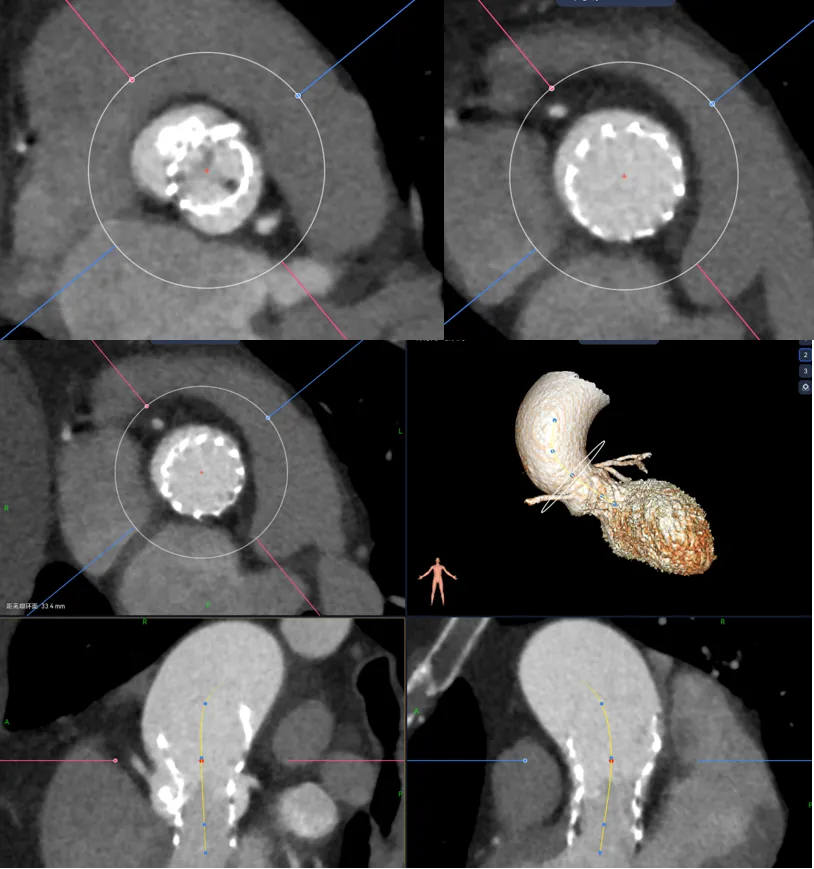

结合下图术后CT可以看到,我对瓣膜位置的预判基本正确,钙化与升主的限制共同把瓣膜推向小弯侧,这时候可以看到瓣膜距离冠脉开口非常之近,如果再贴近一点,瓣膜植入再高一点,裙边或者吊桥可能会有冠脉阻挡风险。所以像这种单边钙化的冠脉风险也是需要看看的。

在这个病例中,我们能够看到升主对于瓣膜的推挤还是很大的,我们既往对于升主的长度有些人会用来评估同轴性,但是很多喜欢量中间来跟支架长度作对比,但实际上要量大弯侧边缘的到转弯地带的长度。

另外还可以看到二叶瓣的瓣膜植入进去,实际上瓣环那边是空的,虚拟瓣环没有任何锚定和封堵作用,实际上的锚定和封堵都是靠瓣上空间。二叶瓣的瓣膜选择需要抛弃依赖瓣环这个习惯。要综合考虑瓣上限制,过大oversize会导致框架扩张不充分(内折或者过度压缩)、瓣叶卷曲等影响血流动力学。笔者一直很反对过度的oversize。